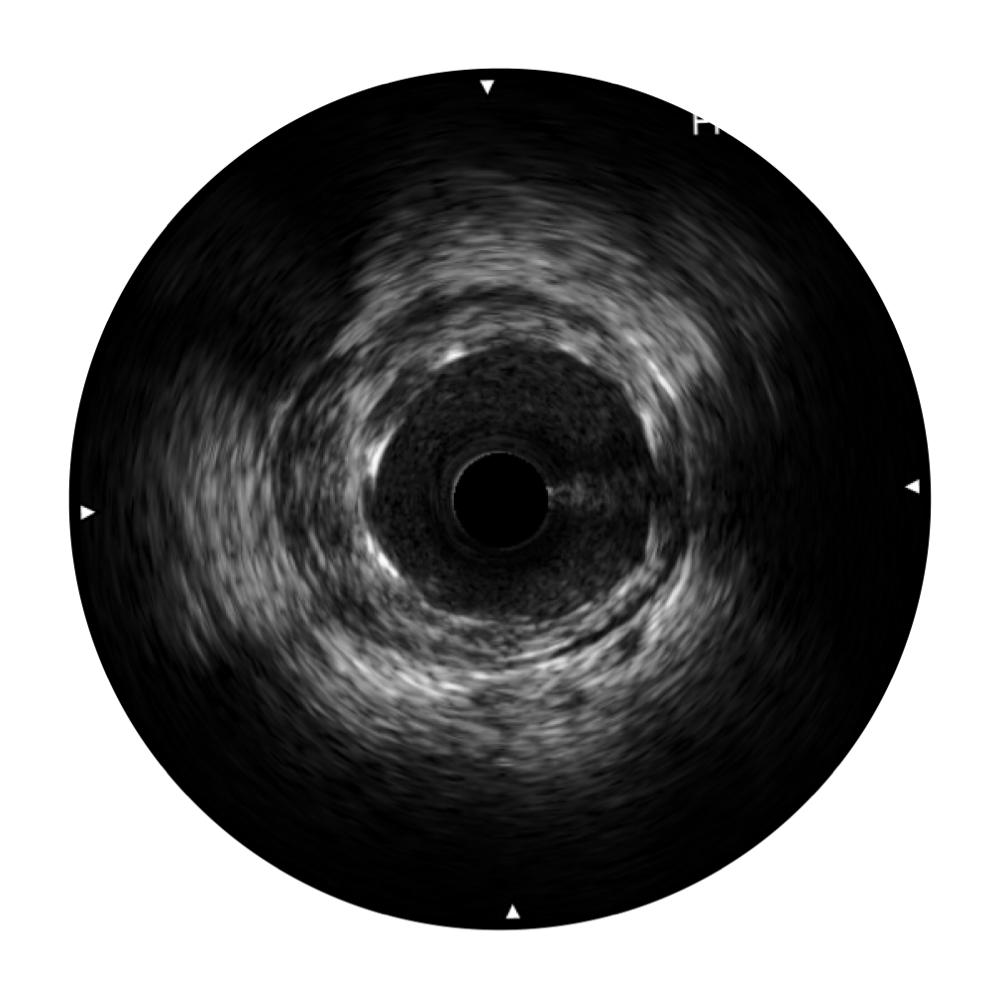

• 诸侯快讯官网宽频IVUS图像

对比传统IVUS导管成像,诸侯快讯官网宽频IVUS图像的近场支架梁显影更细腻,远场中膜外血管仍清晰可辨,兼顾远中近,兼顾分辨力与穿透深度